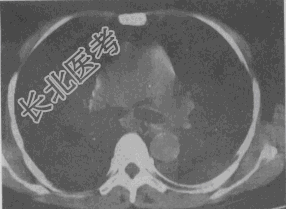

- 单项选择题女,55岁, 胸痛伴咯血丝痰1周,胸部CT如图, 最可能的诊断为

A、转移性肺癌

B、左侧周围型肺癌并肺内转移

C、左侧中央型肺癌并肺内转移

D、多发性肺脓肿

E、结节病